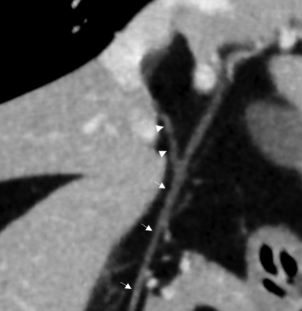

CT로 보는 라브라도 리트리버의 담도 직경

세부 항목은 각자 보는것으로 하고 눈에 띄는부분은 정상적인 총담관의 직경이다.

가작 두꺼워 봐야 4.5mm 이다.

하지만 꼭 기억해야 할것이

1. 이건 관광의 두께가 아니라 내부 공간을 포함한 담도 전체의 직경을 말하는것이다. 즉, 내부 관광은 훨씬 좁다는것을 의미하고

2. 대형견에 해당하는 라브라도가 기준이라 더 작은 개체인 소형견을 생각한다면

한국 수의사들이 생각하는 초음파상에서 총담관은 확장이 없는게 정상이라는 일반적인 추론은 합리적인 의심이란것이다.